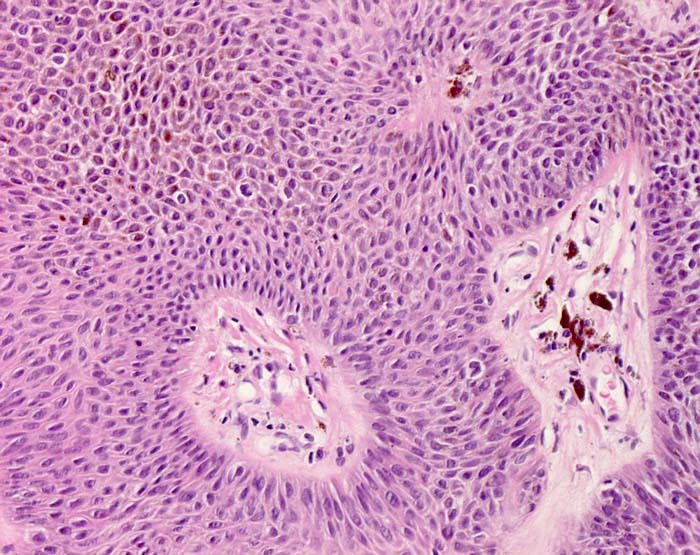

Basel 2BA/ Seborrhoische Keratose

Seborrhoische Keratose

Histologie:

Die grosse makroskopische Vielgestaltigkeit widerspiegelt sich auch in einer variablen Histologie. Unterschieden werden mehrere histologische Subtypen der seborrhoischen Keratose: Hyperkeratotischer Typ (> 3435), akanthotischer Typ (Kurspräparat), klonaler Typ (> 7284) (> 7285), irritierte seborrhoische Keratose (> 3353) (> 3356). Typisch für seborrhoische Keratosen sind umschriebene Wirbelbildungen von Tumorzellen, sogenannte squamous eddies (> 8065). Der retikuläre Typ (> 7838) entwickelt sich in chronisch UV exponierter Haut meist im Gesicht und geht oftmals hervor aus einer solaren Lentigo (> 7839)

Morphologische Merkmale:

• Erhabener (=exophytischer) Tumor

• Verdickte Epidermis (Akanthose)

• Keratingefüllte Epidermisinvaginationen und Hornzysten mit konzentrisch geschichteten Hornlamellen.

• Vernetzte Zellstränge bestehend aus monomorphen basaloiden zytoplasmaarmen Plattenepithelzellen.

• Herdförmige starke braune Pigmentierung der Tumorzellen.

• Perivaskulär betonte, oberflächlich dermale lymphohistiozytäre Entzündung mit Melanophagen. Das sollte der Kliniker dem Pathologen mitteilen: